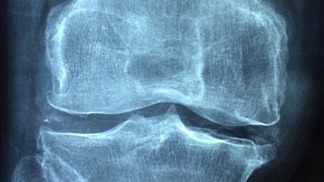

Nemoc přichází pomalu a většina pacientů si prvotních příznaků ani nevšimne. Proto si vysloužila přezdívku ‚tichý zloděj‘ - člověka obírá o kosterní hmotu tak dlouho, dokud na problém neupozorní první zlomenina. V tu chvíli už stačí jen minimální náraz nebo upadnutí. Nejvíc náchylné k frakturám bez zjevných příčin bývají obratle, krčky stehenních kostí nebo předloktí.

Mnoho lidí své problémy mylně pokládá za přirozený projev stárnutí. Zakulacující se záda, snížení výšky postavy i o tři centimetry, bolesti páteře a dlouhých kostí nebo potíže při hlubokém nádechu do břicha nepovažují za podstatné a přehlíží je. Včasná diagnostika přitom výrazně napomáhá zpomalit nebo zastavit progres nemoci.

Jak uvádí Státní zdravotní ústav, osteoporózou trpí sedm až deset procent světové populace, převážně starších ročníků. Vzhledem ke zvyšování průměrné délky života čísla neustále rostou, přesto je léčeno odhadem jen 10 až 20 procent nemocných. Překvapivé zlomeniny pak bývají v pokročilém věku velkým strašákem, zbavují pacienty soběstačnosti a velmi snižují kvalitu života.